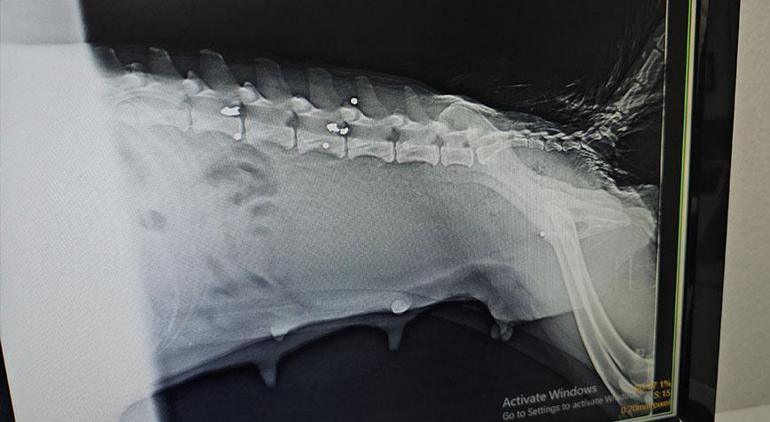

5 yavru dünyaya getiren hayvanseverlerin yaralı halde bulduğu köpek, Zonguldak’ta veteriner kliniğine getirilerek tedaviye alındı. Yavrulardan 1’i hayatını kaybederken 6 saçma isabet eden anne köpek, ameliyat edildi. Arka kısmındaki felç geçmeyen köpeğin sağ arka bacağı ve kuyruğu kesildi. Köpek ve geriye kalan 4 yavrusunun durumunun iyiye gittiği bildirildi.

Köpeğin yaralı, yavruların yeni doğmuş olarak geldiğini ifade eden Veteriner Hekim Ömer Faruk Alkan, “Röntgeni çekip muayene yaptıktan sonra yakın mesafeden ateş edildiğini, saçmaların omuriliğin içine ve vücuduna saplandığını gördük. Omuriliktekini arka tarafı felç kalacağı için saçmayı bulup çıkarttık. Omuriliğin etrafındaki kemik dokusunu serbestleştirerek oradaki sinirin baskısından kurtardık. Sonra yavrularının yanına koyduk. Bir hafta kadar fizik tedavi uyguladık ama 1 ayakta felç olduğunu gördük. Hiç his yoktu. O ayak ve kuyruğu ampute ettik. Diğer ayakta da fizik tedavisi sürüyor. Fizik tedavide lazer ve yürütme egzersizleri yapıyoruz. Şu an ilk geldiğine göre çok iyi ama uzun süre tedavi görmesi gerekecek. Yavruların durumu çok iyi sadece 1 tanesini kaybettik. O da aldığı silah yarasından olabilir. Yavrular bize yeni doğmuş şekilde geldi” dedi.